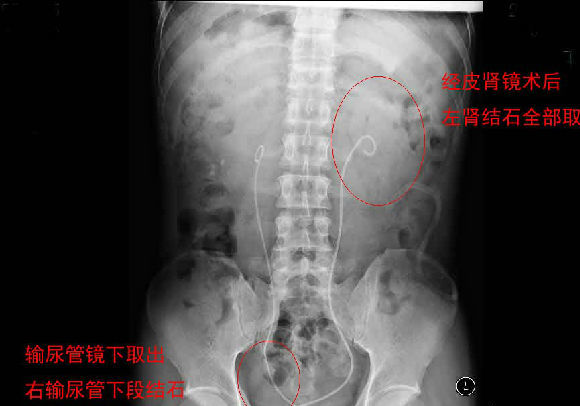

每天早上手术间响起泌外医生们特有的交谈声音和机器们互相的运转声交替成了一道熟悉不变的旋律,从手术室护士摆着各种专用体位,推着各种器械,液体进进出出,医生们应用着各种碎石手段消灭石头,利用气压弹道、激光、超声等碎石工具,把结石击碎取出,一阵忙碌的节奏。泌尿外科的手术时间都不长,每天手术例数又多,你就会看见这么一群人来来回回,医生护士还是那么个,病人都换了无数。最长一次从早上8点到隔天凌晨2点才结束手术,回到家就立马睡觉都顾不上吃饭。现在手术间正做着一台经皮肾镜下碎石取石术,这是我们医院泌外科的王牌。

经皮肾镜取石术,就是在腰部建立一条从皮肤到肾脏的通道,通过这个通道把肾镜插入肾脏,英文简写为PCNL。经皮肾镜取石术是肾结石治疗的现代微创技术,我院在惠州率先开展此项技术,现在每年进行数百例手术,基本上已经淘汰了开放手术取石。经皮肾镜取石术是一项技术性非常强的手术。我们知道,肾脏是血管非常丰富的器官,肾脏血流占心脏排出血量的1/4。既要尽量避免出血、又要努力取净结石、还要保护肾脏功能,这需要非常精细的手术技术。从某种程度上说,这个手术要比治疗肾癌的肾切除术难度大很多。传统的“开刀取石”的方法,需要在腰部做一个的大切口,切开腰部的肌肉,把肾脏分离出来,在肾盂或肾实质切开一个小口,将结石取出来。这种方法损伤大、出血较多、痛苦重、恢复慢。通常手术后需要住院7天以上。因为手术切口大,不但皮肤不美观,而且手术后患者的体力受影响比较大。与开放手术相比,经皮肾镜取石术具有损伤小、痛苦轻、取石彻底、恢复快等优点。腰部的切口通常小,因为不切开肌肉,不但不影响美观,而且手术后对劳动力几乎没有影响。手术后住院时间也明显缩短。与腹腔镜取石相比,经皮肾镜取石术对肾脏及周围的结构影响小,不影响以后的各种肾脏手术。与体外碎石相比,它的治疗周期短、效果立竿见影,对肾功能的影响也较小。(手术室/麻醉科 阮伊莎)